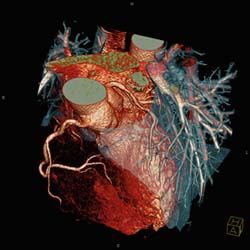

Multislice CT angiography can save lives by identifying occult congenital cardiac anomalies and disease that could lead to sudden cardiac death among competitive athletes.